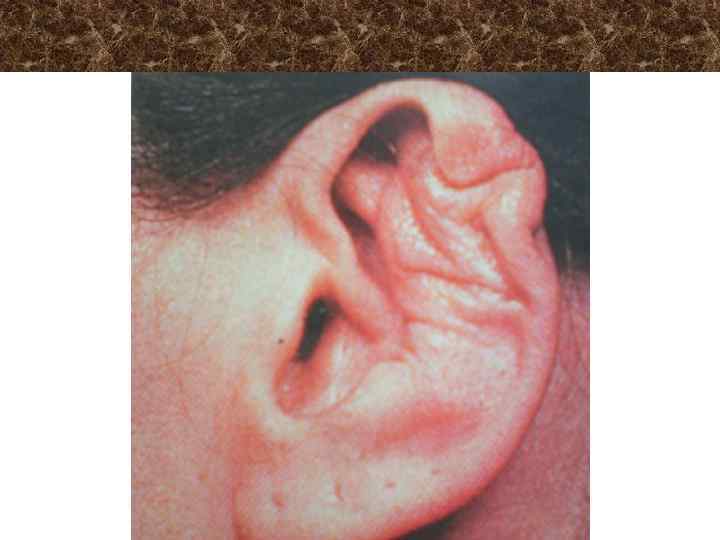

Синдром 2 жаберной щели ü ü ü ü Торчащие уши Дефект мочки Дефект противокозелка Гофрированная ушная раковина Расщелина ушной раковины Недоразвитие слуховых косточек Снижение слуха